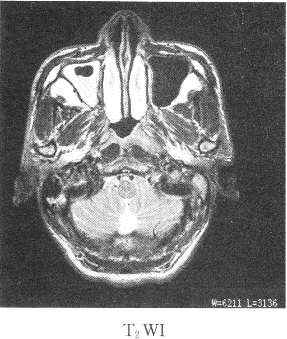

患者男性,39岁,因耳鸣,听力下降来院,影像学检查如图所示

1.该患者最有可能的诊断是

正确答案:1.C;2.B;3.ABDE 解题思路:鼻咽癌我国以广东省为高发地区,男性多于女性,好发于鼻咽顶壁,其次为侧壁,前壁和底壁极少。